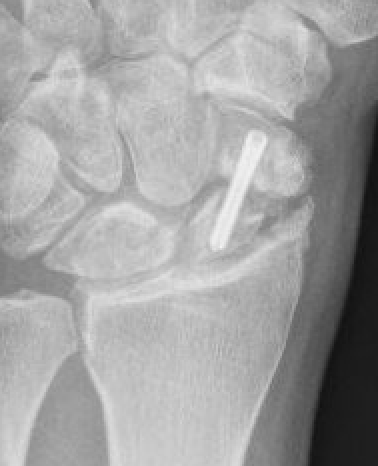

Post scaphoid ORIF

Xray

Nonunion with minimal displacement and minimal resorption

Nonunion with significant displacement and bone resorption

Proximal pole fracture with displacement and absorption